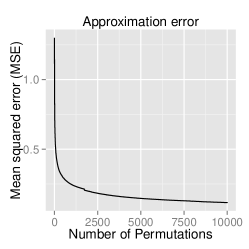

Analytical approximation of p-values

To confirm that the analytical approximation of null distribution of GDM is correct, we estimated the p-values through the approximation technique as well as through permutation testing. A range of 10 to 10,000 permutations was applied to observe the error rate. This experiment was performed on the ADNI dataset. The results displayed in figure 1 demonstrate that the analytic approximation holds with approximately error.